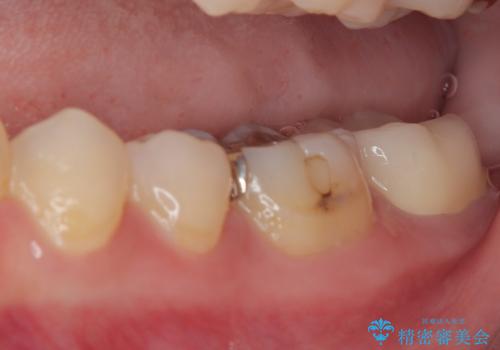

右上のインプラント治療は、1DAYインプラント治療(抜歯即時埋入・即時荷重)の適応となりましたので、通常3回必要な外科処置の回数を1回に集約させることができました。

口腔内の環境が大きく改善し、現在はご自身のプラークコントロールにより良い状態が維持できるようになりました。